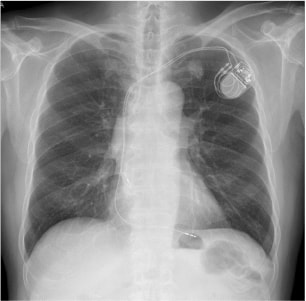

ペースメーカ植込後(X線写真)